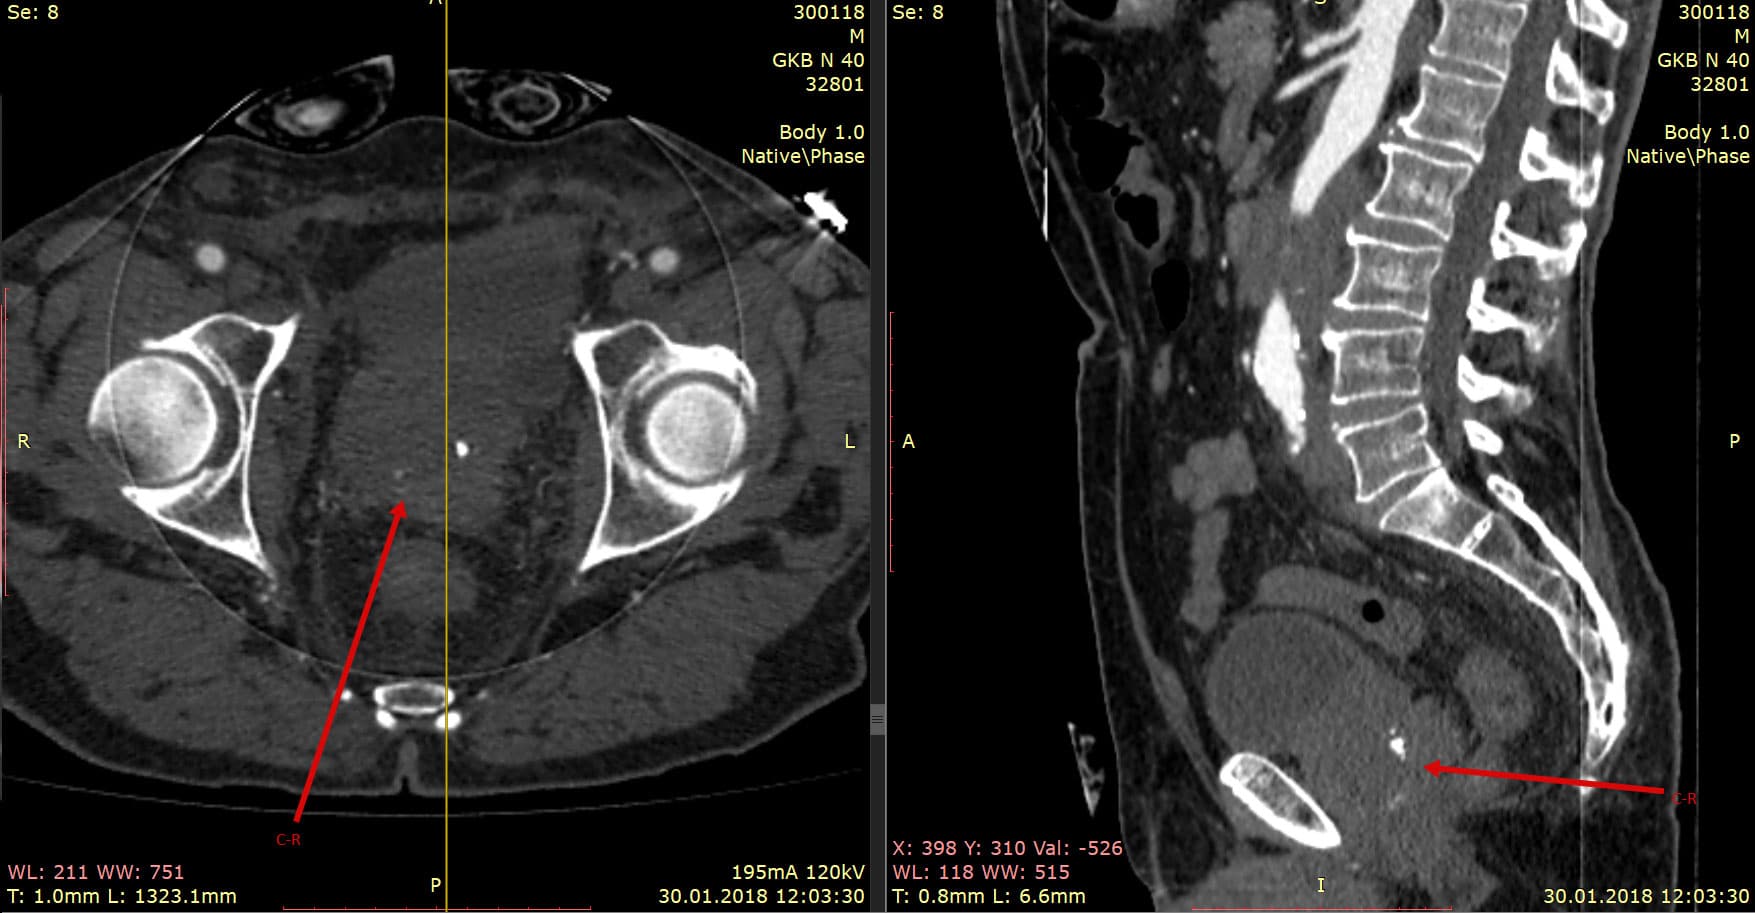

Сама процедура КТ брюшной полости с контрастным веществом представляет собой сканирование органов брюшной полости с использованием специального аппарата. Пациент ложится на стол, который скользит внутрь тоннеля сканера. Во время сканирования важно лежать неподвижно, чтобы изображения получились четкими и точными.

Во время процедуры пациенту могут ввести контрастное вещество через вену для более детального изучения органов. Контрастное вещество помогает выделить сосуды, опухоли или другие изменения в тканях, делая результаты более информативными.